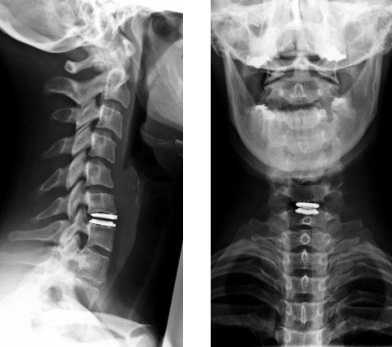

Как правило, назначается процедура рентгена шейного отдела позвоночника в двух проекциях - боковой и прямой. Дополнительно может назначаться косая, если нужно детально рассмотреть межпозвонковые отверстия.

Рентген шейного отдела позвоночника в двух проекциях

Чаще всего процедура выполняется в обычной прямой и боковой проекциях. Как правило, такого исследования достаточно, чтобы оценить состояние позвонков и определить причину жалоб пациента. По получении снимков могут быть назначены дополнительные исследования, которые позволят оценить состояние мягких тканей шеи, либо же будет прописано лечение, если информации окажется достаточно.